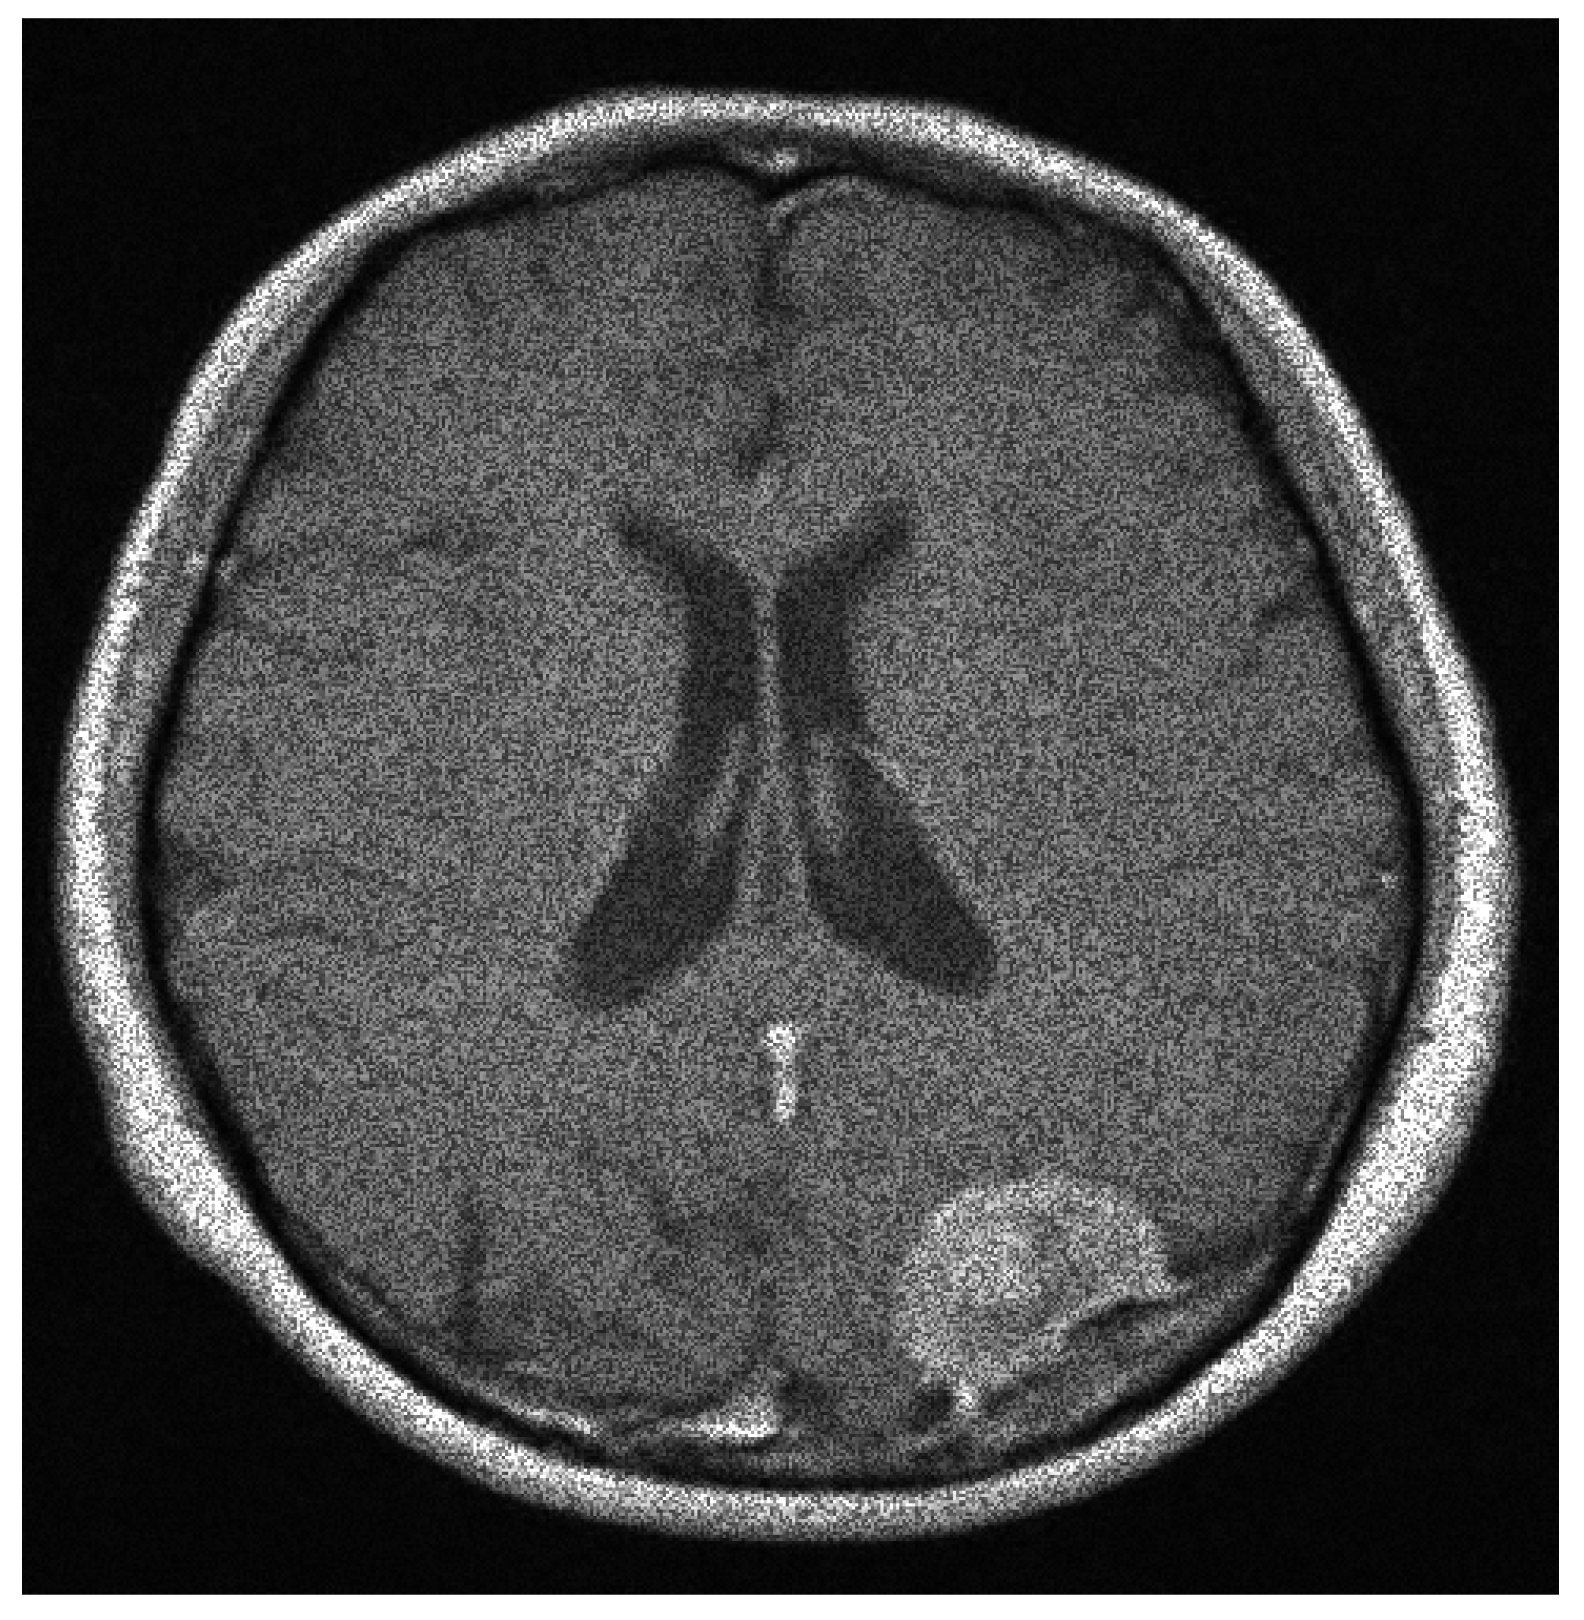

Moreover, and by accepting the fact that there is no still a satisfactory performance measure index for a image segmentation process [13]. So far, we utilize the subjective evaluation criterion [13]. However, it is important to note that even when this criterion is widely used, an untrained subjective evaluation may result in a mistake conclusion [13]. Then, by suing the subjective evaluation measure to our processed noisy images, our technique, and according to our numerical experiments, presents an acceptable performance. On the other hand, the Jaccard similarity coefficient has also been extensively used for the performance evaluation of image segmentation methods. Recall that the Dice similarity coefficient is related to the Jaccard one. Essentially, the Jaccard coefficient, also known as the Tanimoto coefficient, measures the overlapping of two given sets, or two images in logical format, where a value of zero indicates no overlapping, and a value of one indicates a perfect agreement. Hence, if two segmentation processes are going to be compared, the one with the bigger Jaccard coefficient (or closer to one) value will have the better performance. Therefore, we proceed as follows in order to validate our performance segmentation algorithm by employing this Jaccard similarity coefficient in comparison to the reference method. Given the original image shown in Figure 12, we add the speckle noise to it. See Figure 13. Then, by utilizing this noisy image, the processed segmentation results are depicted in Figure 14. Then we transform the clean image into a binary image (logical format) by invoking the command im2bw of Matlad with a thresholding level of . We called it Image A. After transforming the colored images shown in Figure 14 into gray-scale images, we also transform them to their binary formats by employing the same previous command at the same thresholding level too. We call them Image B and Image C, respectively. That is, Image B is the resultant binary image of our processed image, and the other one coming from the corresponding reference method. Now, we are interested in comparing the similarity between Image A and Image B with respect to the similarity between the Image A and the Image C by invoking the Jaccard method. By doing it, we obtain and , respectively. Hence, our approach has a better performance.

Figure 13.

The speckle noisy image with .